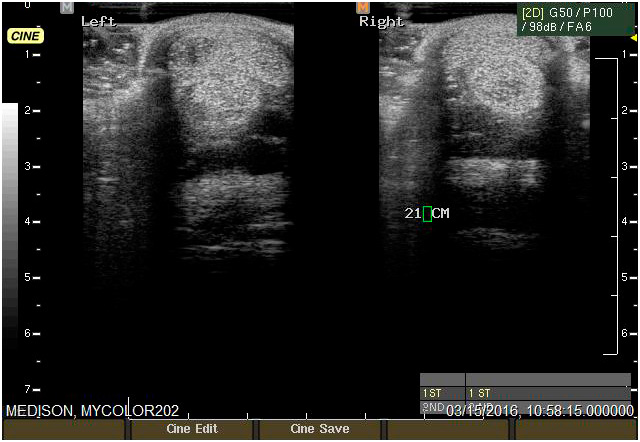

Ecografía

Cuenta con Ecografía digital de alta complejidad.

17 años de experiencia siendo una de las ecografistas más reconocidas en la práctica de equinos. Realiza pasantías en la universidad de Davis California y en Mid-Atlantic Equine Medical Center en New Jersey.